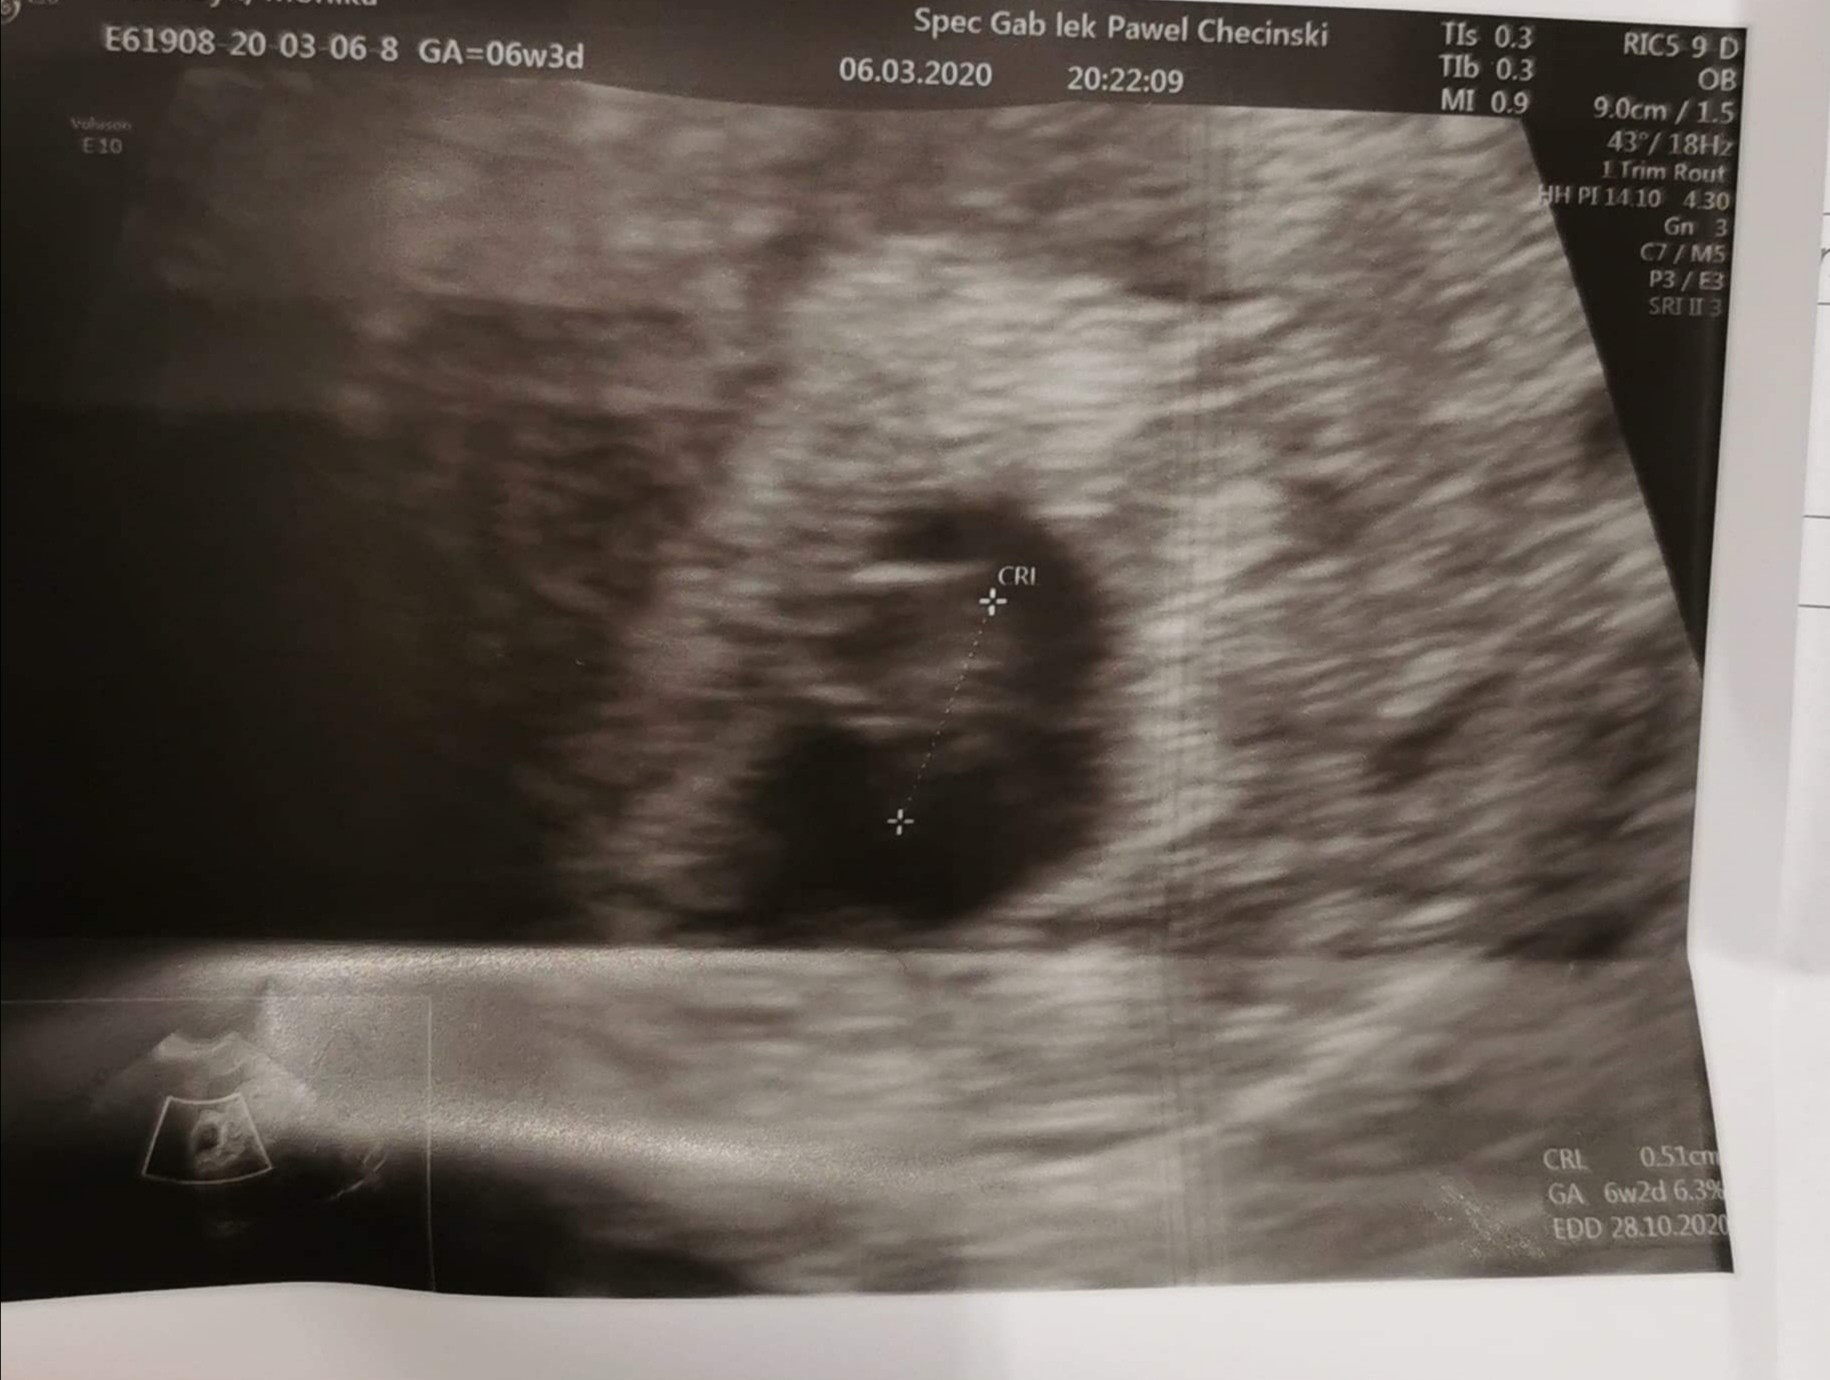

Mamy serduszko♥️🥰

Załączniki

• IMG_20200306_211805.jpg

IMG_20200306_211805.jpg

273,7 KB · Wyświetleń: 103